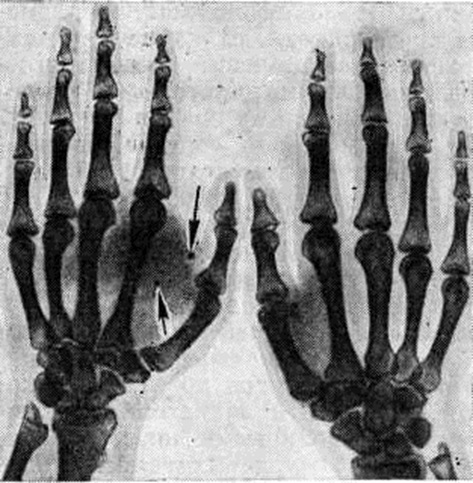

Нередко вторичное вовлечение кости при первичной Гемангиома мягких тканей (рисунок 3); на фоне клинически и рентгенологически выявляемого увеличения объёма мягких тканей определяются типичные мелкие (костной плотности) образования — ангиолиты. Иногда наблюдается истончение участка кости, соприкасающегося с опухолью от давления, причём остеопороз, как правило, отсутствует. При прорастании Гемангиома в кость в зоне её внедрения наблюдается развитие центральных и краевых дефектов, окружённых склеротической каймой.

При Гемангиома мягких тканей предплечья и голени обычно наблюдается вовлечение в процесс обеих костей на уровне локализации Гемангиома. Рентгенологическое исследование подтверждает диагноз Гемангиома, выявляя в мягких тканях характерные тени ангиолитов.

Дифференциально-диагностические трудности, возникающие при глубоком расположении Гемангиома в мягких тканях, могут быть разрешены при помощи ангиографии (рисунок 4).

Рис. 3. | ||

Рис. 4. | ||